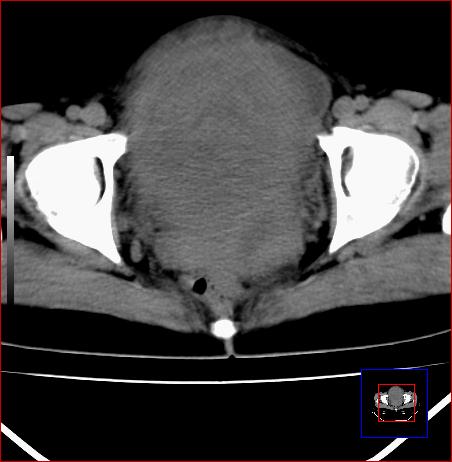

标题: CT15141:子宫肌瘤还是卵巢肿瘤 [打印本页]

腹部包块1年余,近两月明显增大,月经量多

子宫占位,恶性可能,确诊需要妇科诊刮。

子宫占位,恶性可能----肉瘤?

考虑子宫腺肌症;不排除子宫肌瘤。